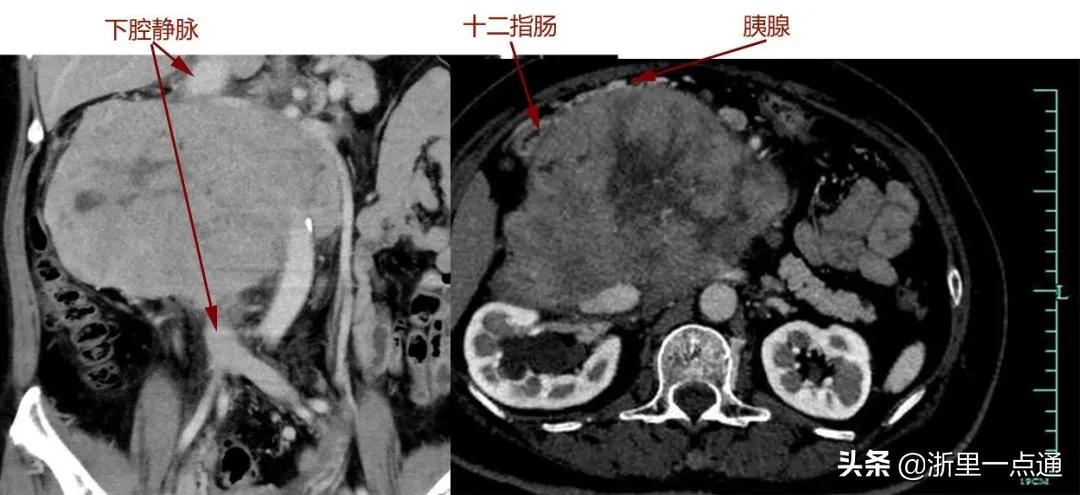

很快,吴女士转院至浙大一院肿瘤外科,完善各项术前检查后,滕教授发现情况远比最初判断严重:肿瘤与胰十二指肠、肾脏等多个脏器及主干血管关系不清,直接吞噬了腔静脉,双肾血管受累,已有轻度肾功能异常。

“我们做过很多类似的手术,但像她这样与血管黏连这么牢的很少。”滕教授表示,随即组织了放射科、泌尿外科、血管外科、肛肠外科、麻醉科、输血科等进行会诊,制定严密的手术方案。针对术中血管与脏器保留或重建的关键问题,他与肛肠外科主任、小肠移植专家吴国生教授,血管外科主任张鸿坤进行了反复探讨,“肿瘤吞噬了腔静脉,这是人体最重要的血管,就像下水管一样,稍有不慎就会大出血,造成不可挽回的后果,而肿瘤如果侵犯肠系膜,可能还要做自体小肠移植。”

手术过程和预计的一样凶险,手术团队小心翼翼将肠道、肾脏血管从肿瘤成功分离。但真正的困难很快出现:肿瘤与胰腺头部黏连,下腔静脉也被侵犯,滕教授当机立断,切断十二指肠及胰头,游离肿瘤两端下腔静脉,最后分离切除大血管部分肿瘤。由于肿瘤向血管内生长,肿瘤切下的同时血液一涌而出,早有准备的团队立即阻断下腔静脉以控制出血,快速切除肿瘤,张鸿坤主任随即缝合修补下腔静脉。万幸的是,术中发现肿瘤与肠系膜血管黏连不严重,避免了自体小肠移植。